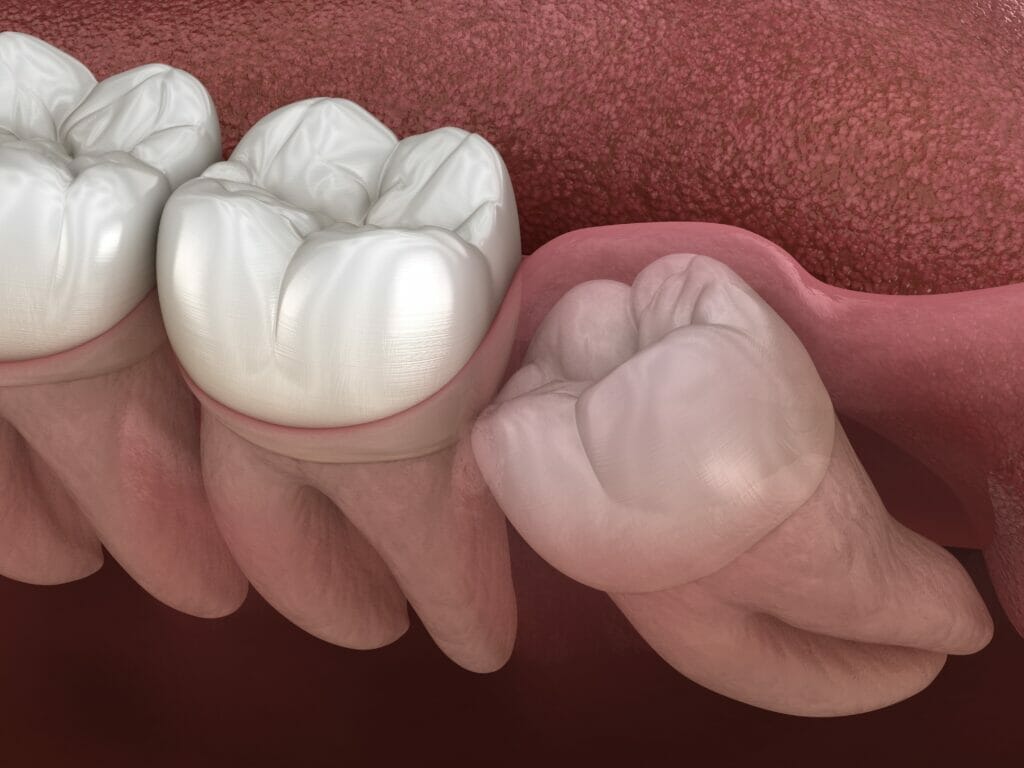

An impacted wisdom tooth is one that is unable to fully erupt. This is commonly due to obstruction from an adjacent tooth or jawbone. The most common type of impaction results in a tooth partially covered by gum tissue. The result is a tooth that is very difficult to properly clean.

Most patients are concerned about what they might feel with an impacted wisdom tooth. Others ask about potential damage to adjacent teeth. Here are some of the possible consequences of long-term wisdom tooth impaction: